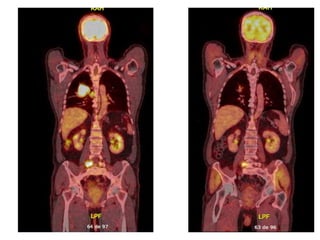

PET CT: 09/16

Lesión Broncogénica 1ª

LN Mediastinico, Hiliar,

Cervical, Implante Pleural.

Compromiso oseo.

Retomando Caso Inicia QMT1ºL: (2016 Septiembre-Diciembre) - Etoposido + Cisplatino. 6 Ciclos Sin Toxicidad. Control con Imágenes : - PET CT Nov 2016 - RM Cerebro Enero 2017

• #6 Masa pulmonar central en el lóbulo superior derecho compatible con lesión broncogénica primaria. Conglomerados adenopáticos mediastínicos, hiliar y cervical bajo derechos, implante pleural ipsilateral y compromiso óseo multifocal secundarios. Nódulo retroperitoneal en fosa ilíaca izquierda sospechoso de localización secundaria. Nódulo pulmonar en el lóbulo superior izquierdo, bajo la resolución del estudio PET